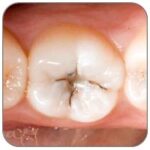

Cos’è la carie dentaria?

La carie dentaria – come riportato sul sito web del Ministero della Salute – è una malattia infettiva a carattere cronico-degenerativo ad eziologia multifattoriale. Colpisce circa l’80% della popolazione nei Paesi sviluppati e si forma per un iniziale processo di demineralizzazione dei tessuti duri dei denti (smalto, dentina), a causa della produzione acida della placca batterica presente sulle superfici dentarie.

Più semplicemente è un’infezione degenerativa di smalto e dentina – i tessuti duri del dente – causata dalla presenza di batteri all’interno del cavo orale. Questi batteri, con il tempo, erodono la superficie del dente procedendo poi verso l’interno fino a raggiungere la polpa dentale, e provocando quindi dolore e infiammazione.

Questi batteri si nutrono di residui alimentari (in particolare di zuccheri), e producono come conseguenza un pH acido che poco a poco erode lo smalto dentale rendendolo poroso e fragile.

Quando lo smalto dei denti viene completamente superato, i batteri raggiungono la dentina e successivamente attaccano la polpa del dente causando dolore e infiammazione.